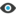

• Biomicroscopy demonstrated advanced age-related macular degeneration (AMD) with GA OU including the perimacular area extending to the foveola in the right eye, while in the left eye, the perimacular retinal pigment epithelium (RPE) remained intact including the foveal architecture. Imaging, including fundus autofluorescence (FAF) and OCT, were used to confirm these findings (Figure 1).

<p>Figure 1. Baseline fundus autofluorescence (FAF) OD demonstrated a confluent nearly extinguished autofluorescence from the upper to the lower arcade affecting the macula. There was limited remaining reflectivity on the foveola. In the left eye, FAF and OCT demonstrated a perimacular GA lesion; however, there was a large perimacular central island with intact retinal pigment epithelium (RPE).</p>

Figure 1. Baseline fundus autofluorescence (FAF) OD demonstrated a confluent nearly extinguished autofluorescence from the upper to the lower arcade affecting the macula. There was limited remaining reflectivity on the foveola. In the left eye, FAF and OCT demonstrated a perimacular GA lesion; however, there was a large perimacular central island with intact retinal pigment epithelium (RPE).